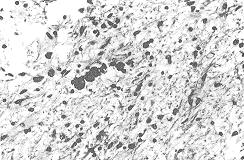

急性壞死性胰腺炎:占急性胰腺炎的10%—20%,胰腺病理改變嚴重,腫大變硬,腺泡及脂肪壞死,血管出血壞死,脂肪壞死可累及周圍組織如腸系膜和後腹膜,病程長的感染後可形成膿腫或瘺管。組織壞死的同時可產生大量血管活性物質,如多肽,緩激肽,組織胺,5—羥色胺,前列腺素,內毒素等。臨床表現為突發的上腹部劇烈疼痛,噁心,嘔吐及中毒症狀,體徵有明顯的腹膜刺激症狀,血性腹水,麻痹性腸梗阻,臍周或兩側腰部有藍色瘀斑,早期常出現重要臟器功能衰竭、休克、少尿、呼吸困難、精神錯亂。後期可出現消化道出血、腹腔出血、重症感染及瀰漫性血管內凝血(DIC)等,CT掃描可發現胰腺腫大,有密度減低區,胰周有積液,CT增強掃描可確定胰腺壞死及壞死範圍。